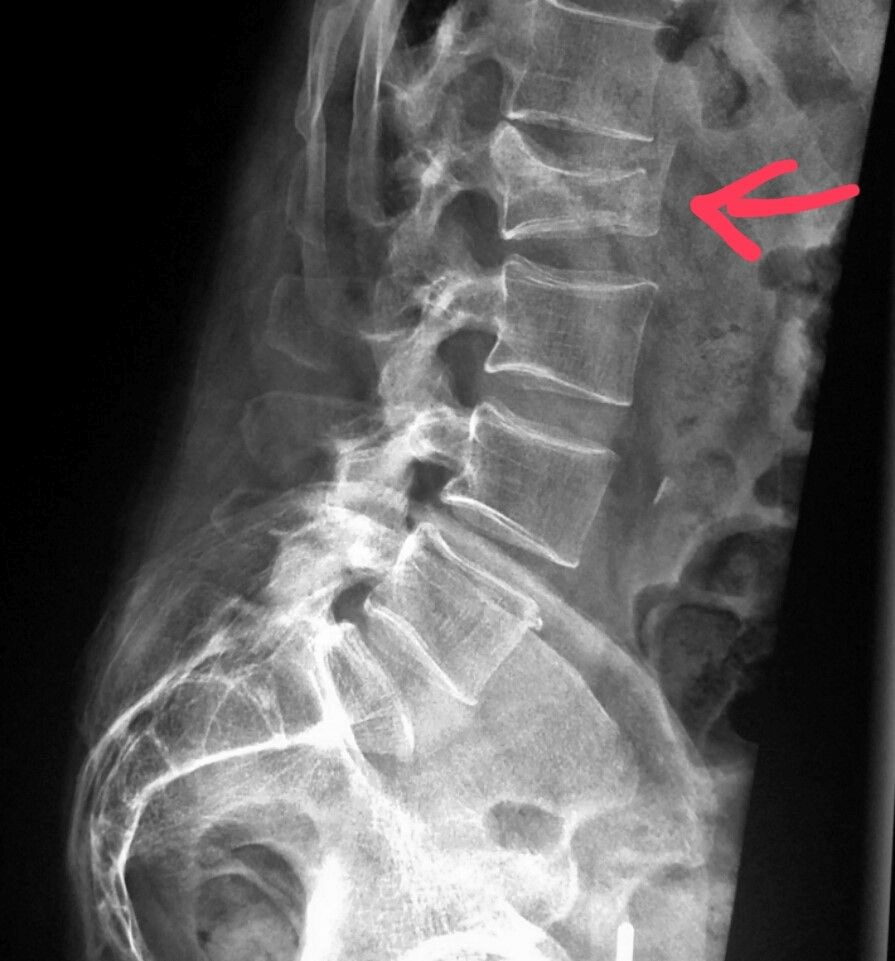

교통사고 충격과 더불어 운전대를 잡고 있던 팔의 어깨 혹은 안전벨트로 고정된 어깨로의 순간적인 충격으로 인해 다양한 형태의 어깨 손상을 입을 […]

교통사고 치료는 일반적으로 차량 보험으로 진행되기때문에 후유증을 최소화하는 단계까지 상당한 치료 기간이 소요됩니다. 교통사고 피해에 대한 보상금 산정은 치료비에 근거하여 […]

교통사고는 아주 약한 접촉사고일지라도 후유증이 발생할 수 있습니다. 사고 직후에는 아픈 증상이 없다가 갑자기 여기저기 통증을 호소하는 경우가 많습니다. 이런 […]

X-ray는 지난 수십년간 우리 주변에서 흔히 접하는 장치로서 실제 몸속의 상태를 확인할 수 있으며, 이로 인해 다양한 의학적 상태에 대한 […]